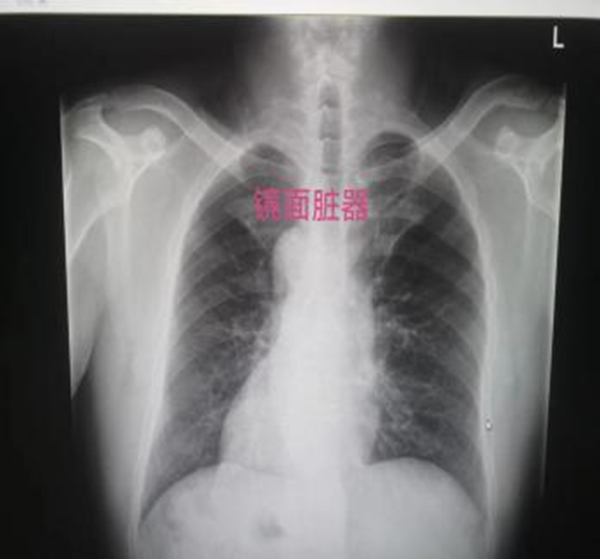

山东高大叔是一个“天赋异禀”之人。普通人心脏均在胸部左侧,而他的心脏却在右侧,同样,高大叔的冠脉血管也都是反着的,医学称之为“镜面右位心”。

高大叔的“镜面脏器”

这个天生的异禀没有给他带来幸福,反而给他带来了痛苦。患者5年前曾因冠状动脉严重狭窄经人推荐找到王健主任,成功完成了冠状动脉介入治疗。